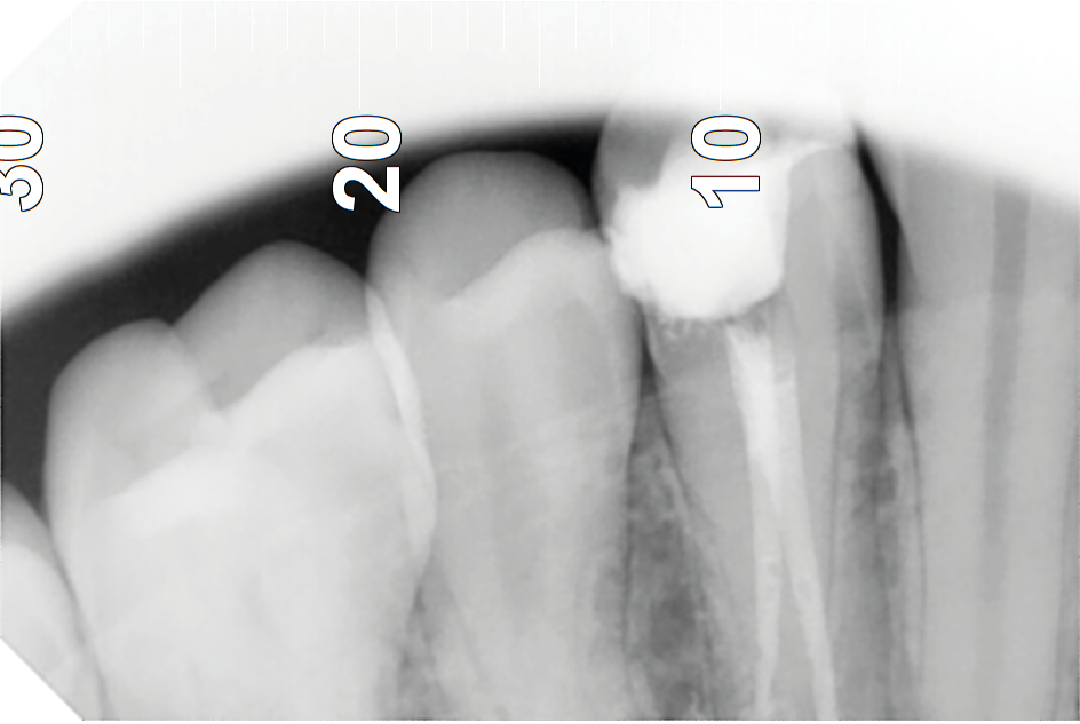

¿Qué es una reendodoncia?

Cuando, a pesar de haber realizado la endodoncia, sigue habiendo dolor y la causa es una infección, se vuele a realizar la endodoncia, mejorando la obturación de los canales radiculares. Si, a pesar de estos intentos, vuelve a doler o hay fractura de la estructura dentaria, se opta por la extracción.